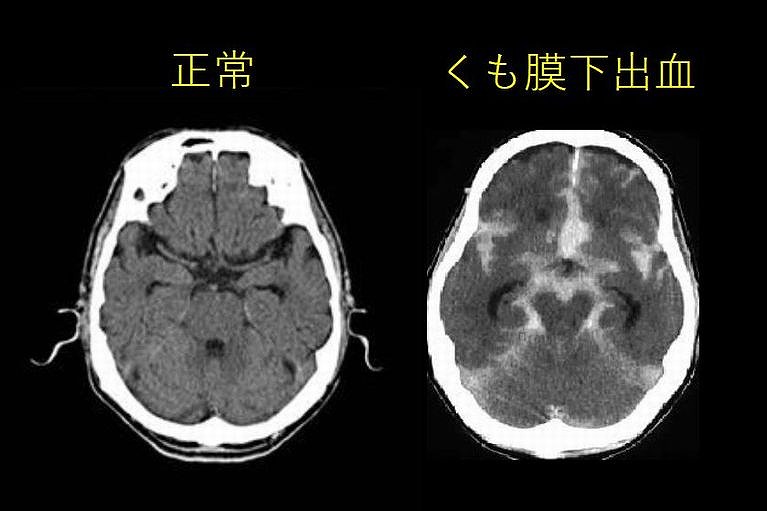

くも膜下出血

• 今までに「経験したことのない」激しい頭痛

• 今までで「最悪」の頭痛

• いつもの頭痛と明らかに違う